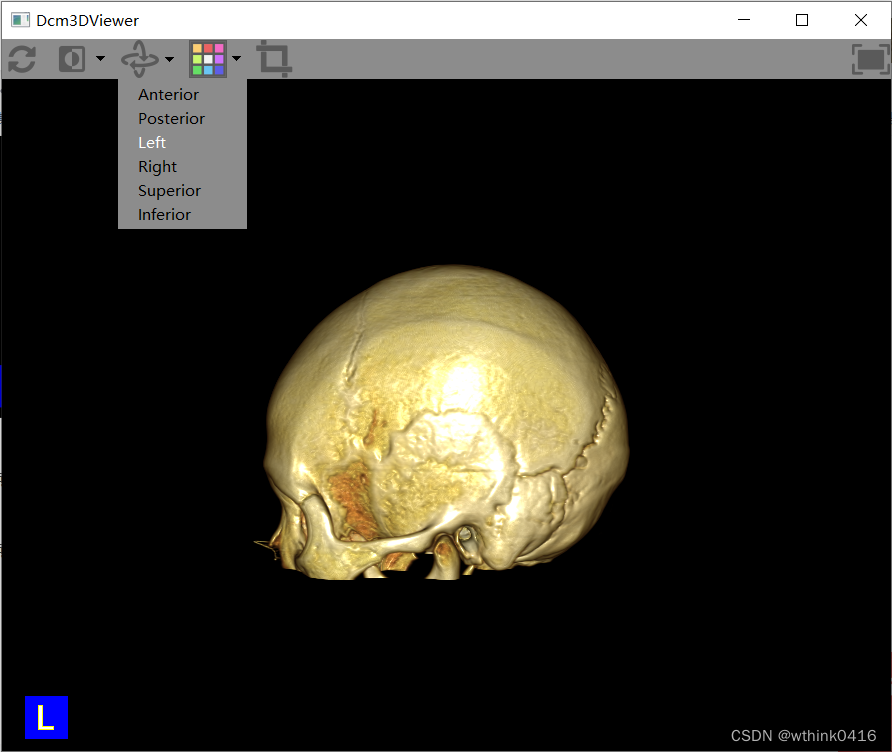

14、点击![]() 旋转图标,鼠标左键移动可自由旋转,下拉菜单支持一些预设角度,可快速切换

旋转图标,鼠标左键移动可自由旋转,下拉菜单支持一些预设角度,可快速切换